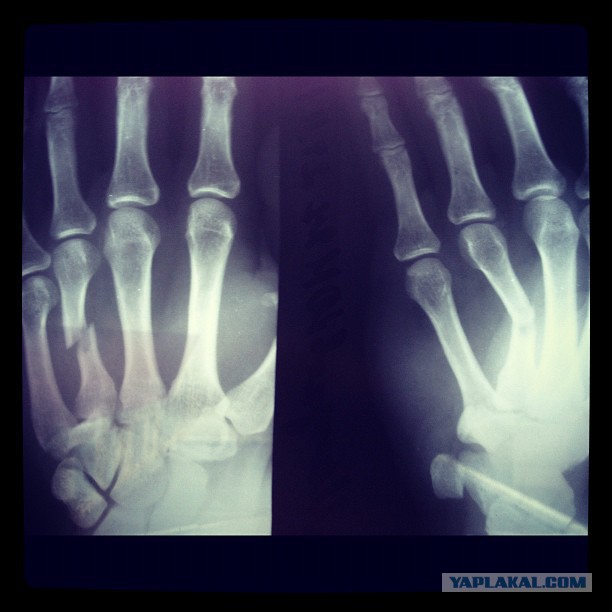

Четвёртая пястная таки не выдержала.

А может надо было просто съебать? Один хуй, никто не увидел бы, ночь на дворе, бегать умею. Прошёл год, здороваться адски больно, мелочь до сих пор проваливается между пальцев, операция по извлечению титановой хуйни запланирована на февраль. Вот сижу и думаю, выиграл я, или, сука, просто лох.

Смотрю на людей, у которых таких шурупов в конечностях насчитывается несколько десятков, конечно пиздец, поколение киборгов поневоле.